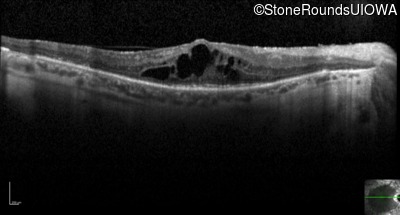

Optical Coherence Tomography - Left - 20/63

Exemplar / OCT Stack